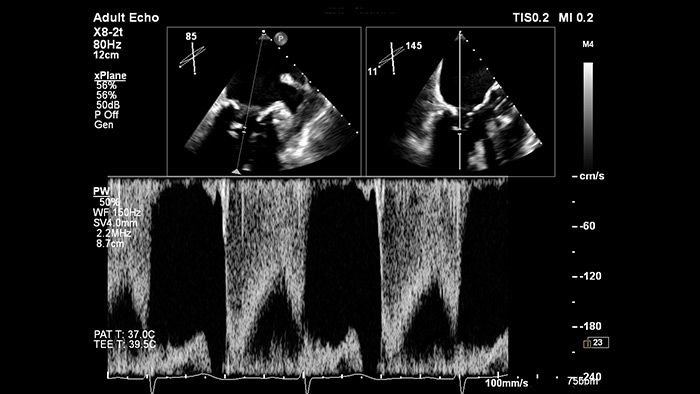

EPIQ CVx - xPlane Doppler

Gain confidence of correct gate placement when assessing cardiac flow with xPlane Doppler